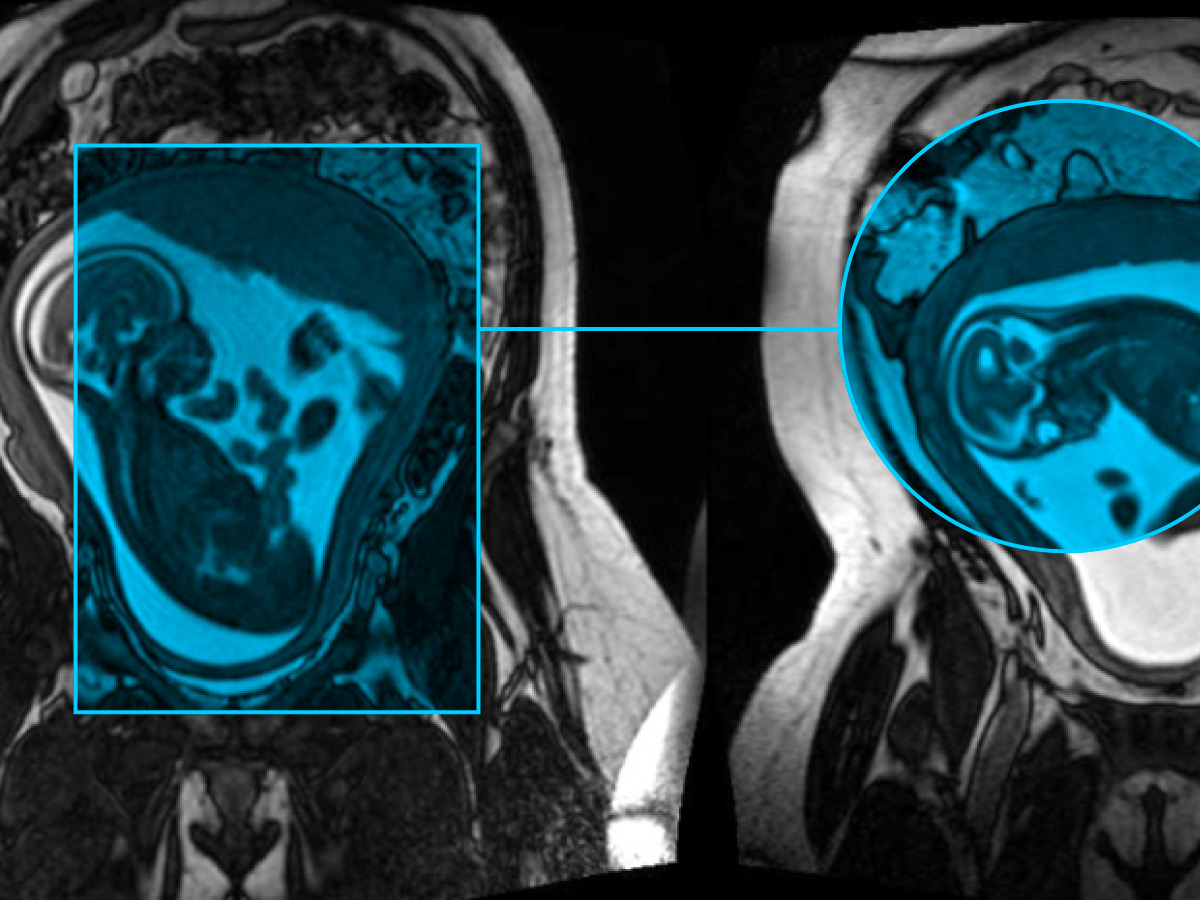

Harnessing AI to transform fetal MRI: Inside the Fetal Assessment Suite

To shorten fetal MRI interpretation times and improve diagnostic accuracy and accessibility, FEAS professor Dafna Sussman developed the Fetal Assessment Suite (FetAS). FetAS is a secure, easy-to-use, web-based platform using machine learning to automatically process fetal MRI scans and help identify potential abnormalities.